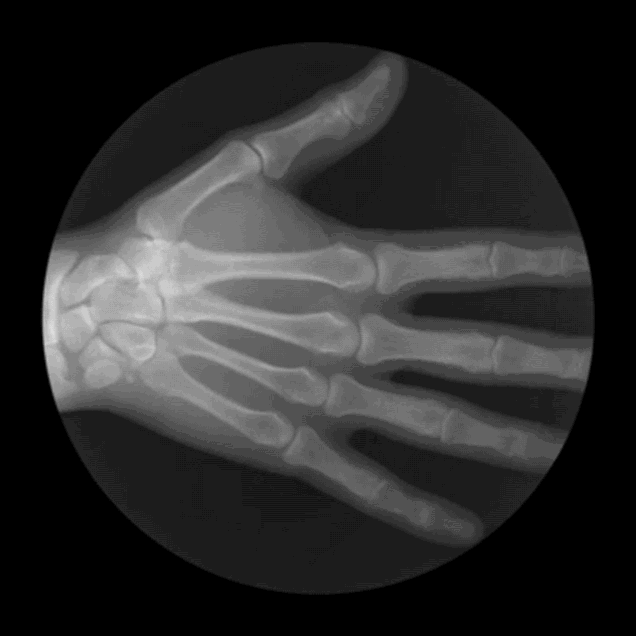

12. Занятный анимированный рентгеновский снимок

.gif)

Графический дизайнер из Сан-Франциско Кэмерон Дрейк создает серии GIF-файлов на основе рентгеновских снимков.